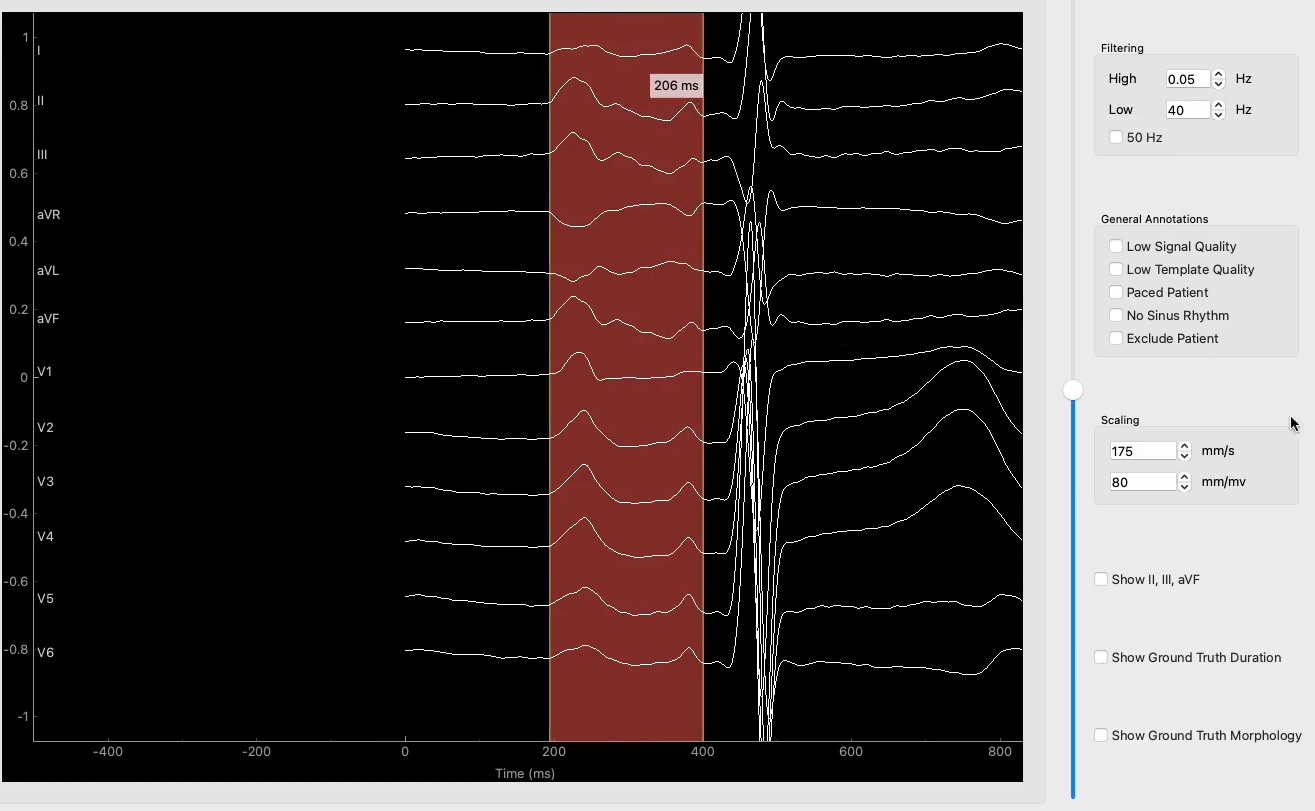

• Atrial cardiomyopathy (AtCM) is associated with slow-conducting low-voltage areas and therefore prolonged total atrial conduction time. Jadidi et al. demonstrated that total atrial conduction time correlates with amplified P-wave duration (APWD). Furthermore, APW morphology has been demonstrated to assist in staging AtCM. These findings suggest that APW duration and morphology measured in a 12-lead-ECG enables the non-invasive diagnosis of AtCM.

Despite its diagnostic value, manual annotation of APWD is time-consuming, subjective, and not scalable, rendering it impractical for large-scale screening or retrospective cohort studies. To overcome these limitations, we aim to develop an automated, AI-based algorithm that can annotate APWD reliably and reproducibly. A critical prerequisite for this is the availability of high-quality expertlabeled ECG data, which will serve as training and validation data for the algorithm.